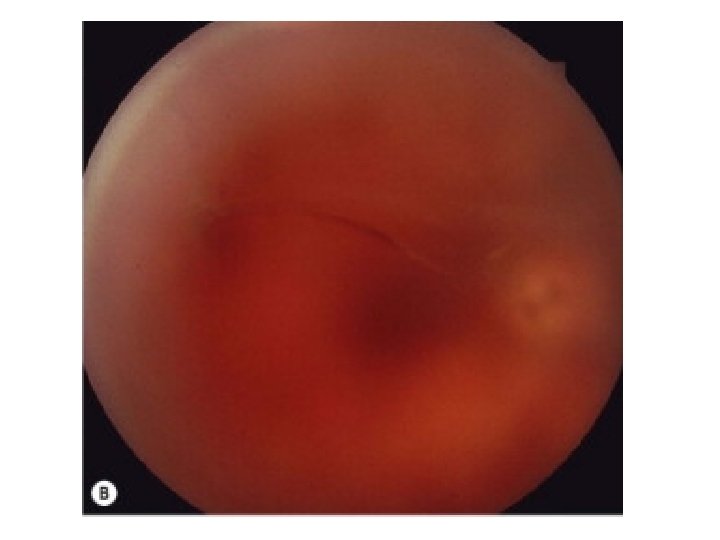

Retinal Detachment • Patients may notice an enlarging shadow in peripheral vision(not just a floater) • Sudden loss of central vision occurs when the macula detaches • Flashes and floaters are common associated symptoms • Ocular history of trauma, surgery and myopia.

Retinal Detachment Acuity normal = macula "on" Acuity poor = macula "off' RAPD Visual field defect corresponding to area of detached retina • Fundus examination is diagnostic (but may be difficult to pick with direct ophthalmoscope) • •